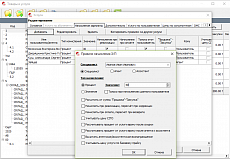

Интегрированное программное обеспечениеFreestep

- Высокая скорость сбора данных

- Автоматические отчеты

- Пространрственно-временные параметры

- Синхронизация видео